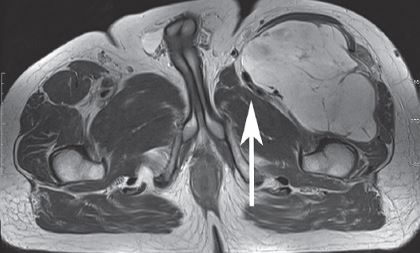

It is a procedure that involves removing a tumor (usually malignant or benign aggressive) of the posterior thigh (hamstring muscles) while preserving the surrounding bone and soft tissues.